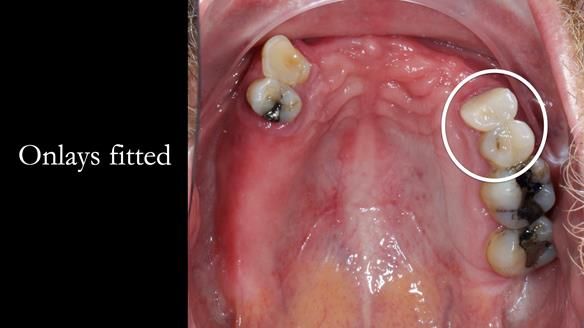

2. Onlay preparations: Composite onlays were fitted for his upper left premolars to repair these teeth and support the new denture.

Keith’s denture incorporated a Duracetal shell clasp on upper right first premolar (Myerson), which are designed to be virtually visible, providing a more aesthetic solution while enhancing patient comfort. The Scandinavian-inspired approach, based in modern removable prosthodontic techniques, ensured the denture was not only durable but also visually pleasing. Additionally, the design was carefully planned to allow for future modifications, ensuring that if Keith loses additional teeth, the denture can be adapted rather than replaced entirely.

I also used the Dahl concept to re-establish the occlusion upon fitting the RPD, which helped to intrude the lower left canine without needing to grind it too much.